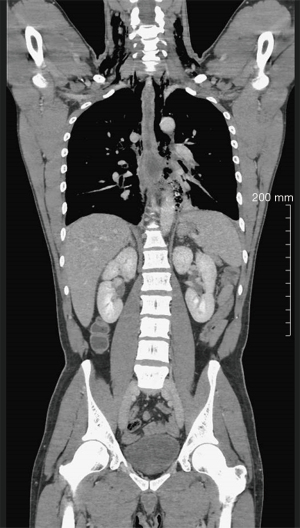

A 38-year-old man without apparent psychiatric/neurologic comorbidities was referred to our hospital 36 hours after the acute onset of dysphagia, drooling and worsening thoracic pain after ingestion of a microwave-heated novel potato. The chest X-ray showed evidence of pneumomediastinum. A chest computed tomography (CT) confirmed the presence of pneumomediastinum, left hydropneumothorax and soluble contrast extravasation (Figure 1). The upper endoscopy showed a 4 cm × 2 cm esophageal full-thickness parietal loss located at 30 cm from the incisors. The mucosal edges of the perforation were scarred and inflamed as occurs in thermal injuries (Figure 2 and Video 1). On arrival, the patient was febrile (38.6 ℃), tachycardic (116 bpm), and tachypneic, with normal blood pressure (130/85 mmHg). The physical examination did not reveal subcutaneous emphysema. White blood cell count (18,500/mm3), C-reactive protein (38 mg/dL), procalcitonin (2.35 ng/mL), and lactate (1.98 mmol/L) were altered. The patient underwent hybrid esophagectomy via laparoscopy and right thoracotomy with gastric conduit reconstruction. A circular stapled 25 mm anastomosis was fashioned at the apex of the thorax and a pleural patch was used to reinforce the suture. Both the right and left chest were drained and a feeding jejunostomy was performed for nutritional support. The postoperative course was uneventful. An upper endoscopy performed on postoperative day (POD) 5 showed regular anastomosis. The patient was discharged home on POD 9 on a soft diet. The histological examination of the specimen did not reveal peculiar alterations. At 8-month follow-up, the patient was doing well with a well-tolerated regular diet. The upper endoscopy showed normal anastomosis and gastric conduit. All procedures performed in this study were in accordance with the ethical standards of the institutional and/or national research committee(s) and with the Helsinki Declaration (as revised in 2013). Publication of this case report and accompanying images was waived from patient consent according to the institutional ethics board of IRCCS Ospedale Galeazzi - Sant’Ambrogio (No. #2023-OGSA1452).